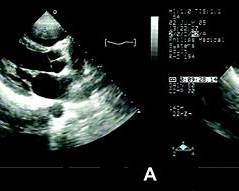

Echocardiography is the gold standard investigation as it defines valve morphology, severity of stenosis or regurgitation, chamber sizes, pulmonary pressures, and complications like atrial thrombus.